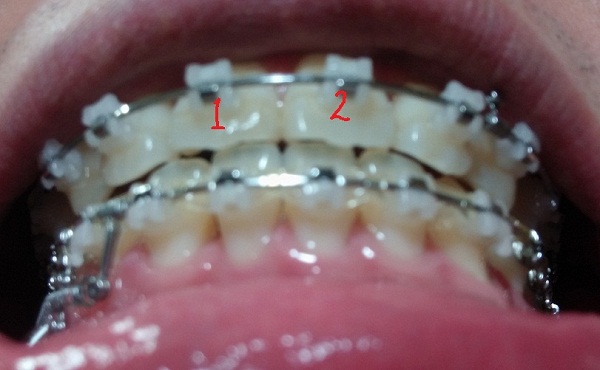

[아래서 본 정면1]

[아래서본 정면2]

현재 교정진행상태

-중심선 99% 맞은 상태!!

-하악 파워체인으로 치아끼리 꽉 조여서 마무리로 가는 중!!

-일회용 고무줄로 치아를 다물 때, 뜨는 공간이 없게

상악 송곳니와 하악 송곳니를 당기는 중!!

지금은 다행히 중심선도 다시 맞고 사진을 보시면 아시겠지만 교합이 거의 맞는 듯합니다.